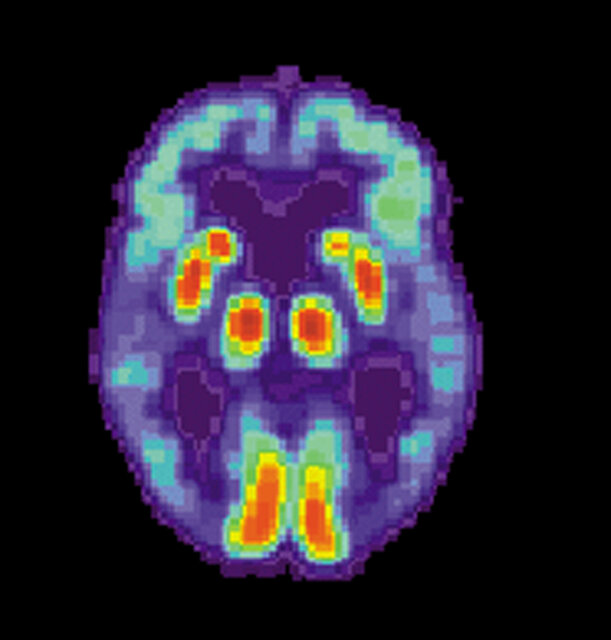

به گزارش ایسنا و به نقل از مدیکالاکسپرس، بسیاری از پژوهشهایی که در مورد بیماری آلزایمر انجام میشوند، بر "آمیلوئید بتا" (Aß) تمرکز دارند. آمیلوئید بتا، پروتئینی است که هنگام رشد بیماری، در مغز انباشته میشود. وجود آمیلوئید بتای اضافه، پلاکهایی را ایجاد میکنند که ارتباط میان سلولهای مغز را از بین میبرند، به بروز التهاب منجر میشوند و نهایتا به از دست رفتن بسیاری از نورونها و بافتهای مغز میانجامند.

پلاکهای آمیلوئید بتا، یک موضوع مهم برای پژوهشهای حوزه آلزایمر به شمار میروند. پژوهش جدید عصبپژوهان "دانشگاه شیکاگو"(UChicago)، فرآیند دیگری را مورد بررسی قرار میدهد که نقش آن در پیشرفت بیماری، به درستی شناخته نشده است.

پژوهشگران در بررسی خود، بر "میکروگلیا"(microglia) تمرکز کردند. میکروگلیا، نوعی سلول ایمنی در مغز است که معمولا سیناپسها را ترمیم میکند، سلولهای مرده را از بین میبرد و پروتئینهای اضافی آمیلوئید بتا را پاکسازی میکند. هنگامی که پژوهشگران، دارویی را که به مرگ سلولهای میکروگلیا منجر میشود، به موشها دادند، عصبزایی به حالت معمول خود بازگشت.

سیسودیا باور دارد که شاید میکروگلیا بتواند به بازگرداندن نقش سیستم ایمنی بدن کمک کند. آلزایمر معمولا به بروز التهاب در میکروگلیا منجر میشود؛ در نتیجه هنگامی که میکروگلیا با سلولهای جدید مغز که به جهش در پرسـنیلین دچار هستند، روبرو میشود، بیش از حد واکنش نشان میدهند و سلولهای جدید را پیش از بلوغ از بین میبرند.